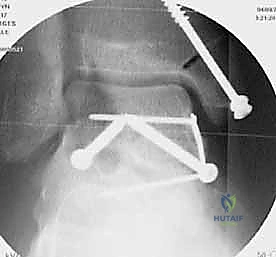

المرحلة الرابعة: التثبيت الداخلي (Internal Fixation)

بمجرد التأكد من أن العظم عاد لشكله الطبيعي تماماً، يتم استبدال الأسلاك المؤقتة بتثبيت دائم. يستخدم الدكتور هطيف أحدث الغرسات الطبية العالمية:

* مسامير التيتانيوم المجوفة (Cannulated Screws): مسامير قوية جداً يتم إدخالها عبر العظم لضغط أجزاء الكسر معاً.

* المسامير بدون رأس (Headless Compression Screws): تُستخدم في المناطق المغطاة بالغضروف، حيث تُدفن بالكامل داخل العظم لكي لا تحتك بالمفصل وتسبب تآكلاً.

* الشرائح المعدنية الدقيقة (Mini-Plates): تُستخدم أحياناً لتدعيم التثبيت في حالات التفتت الشديد (Comminution) حيث لا تكفي المسامير وحدها.

يتم وضع المسامير عادة من اتجاهين (من الأمام للخلف، ومن الخلف للأمام) لإنشاء هيكل ميكانيكي صلب يتحمل الضغوط.

المرحلة الخامسة: التحقق الإشعاعي الفوري والإغلاق

قبل إنهاء العملية، يستخدم الدكتور هطيف جهاز الأشعة السينية المتحرك داخل غرفة العمليات (C-arm Fluoroscopy) لأخذ صور متعددة والتأكد من:

1. المحاذاة المثالية للكسر.

2. عدم وجود أي فجوات أو درجات في السطح المفصلي.

3. الطول والموقع الصحيح للمسامير (للتأكد من أنها لا تخترق المفاصل المجاورة).